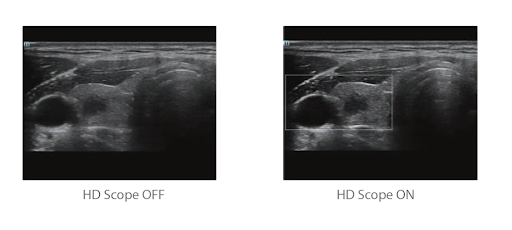

HD Scope™ - технология увеличения пространственного разрешения в зоне интереса

Область HD: более четкое изображение в пределах области интереса